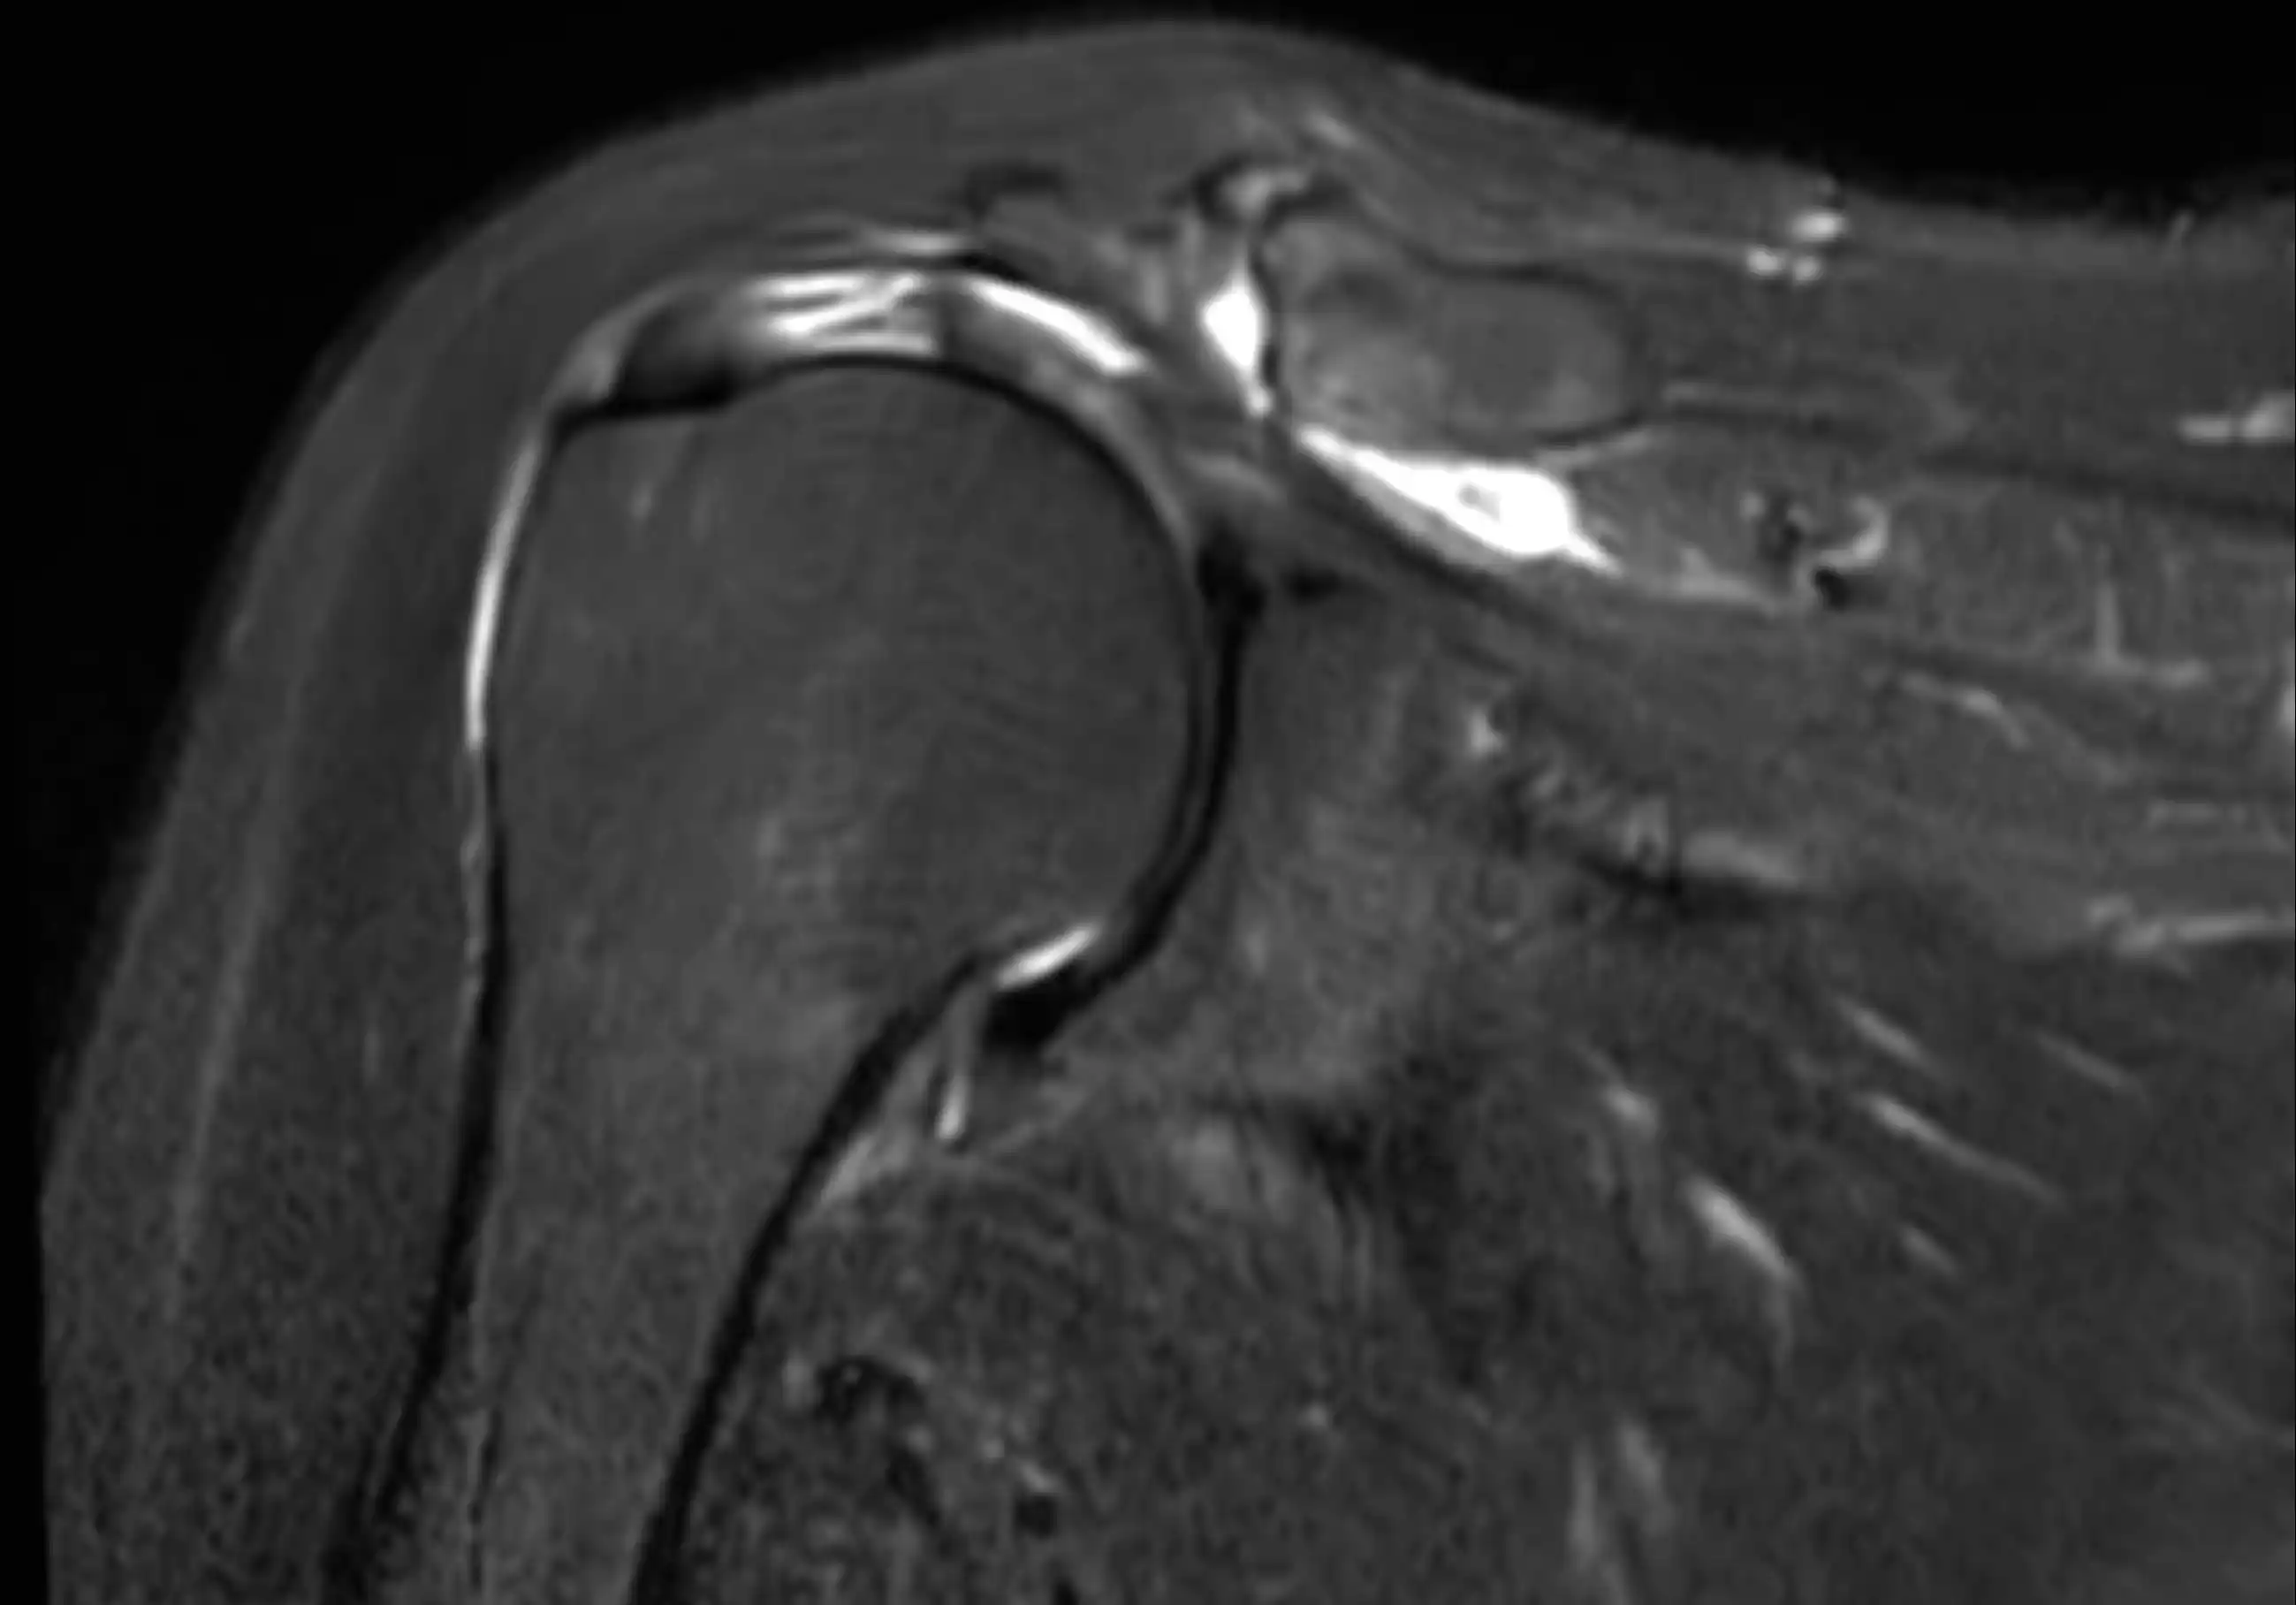

МРТ плечового суглобу — це сучасний метод обстеження, який дозволяє детально оцінити стан кісток, хрящів, зв’язок, сухожиль, м’язів та інших м’яких тканин плечового суглоба.

Магнітно-резонансна томографія є одним із найточніших методів діагностики патологій плеча і проводиться без використання рентгенівського випромінювання.

- пошкодження ротаторної манжети плеча

- патології хряща